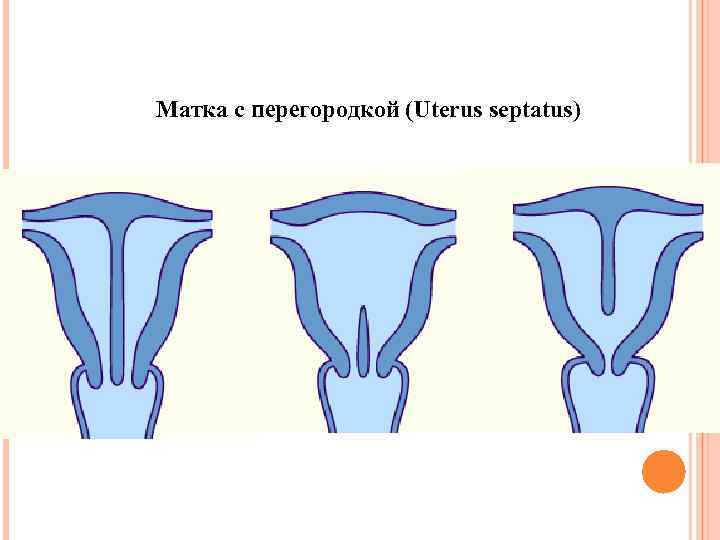

Матка с перегородкой (Uterus septatus)

Матка с перегородкой (Uterus septatus)